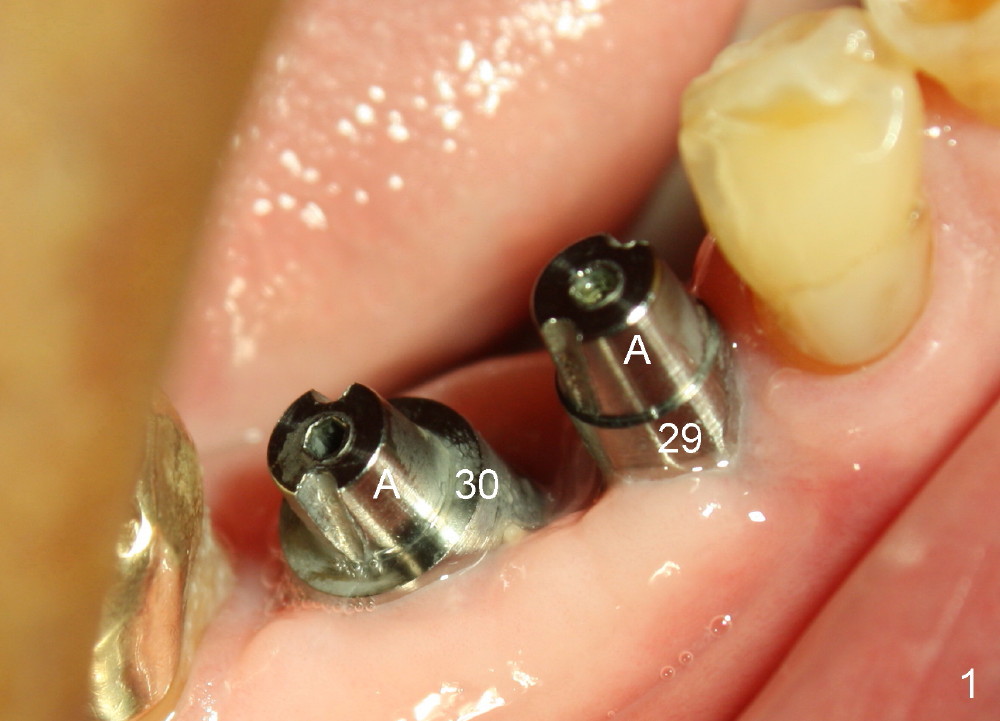

One month after implant placement at the sites of #29,30, the former is found loose (Fig.1,2). It is placed higher than #30. Three weeks later, PA is retaken to confirm that there is space apical to the implant at #29 (Fig.3 double arrows) and that there is distance from the mental loop (yellow dashed line). After infiltration anesthesia, the implant is torqued down initially (compare Fig.4,5) and more (Fig.6,7). To prevent re-loosening, the two implants are splinted (Fig.8).

There are several possible reasons for #29 loosening. Implants are placed almost on the right and left sides at the same time. The patient is a bruxer. Abutments placed immediately are used to hold perio dressing in place. After perio dressing is dislodged, the patient may chew with the abutments. There is distal wall defect associated with #29 socket when the tooth is extracted and socket preservation is done.